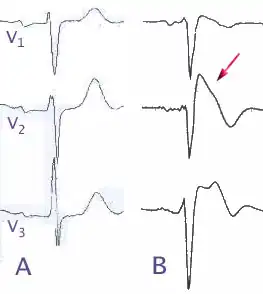

![]() (А) — нормальная ЭКГ в правых грудных отведениях (V1-V3); (В) — изменения при синдроме Бругада | |

Синдром Бругада характеризуется наличием преходящей полной или неполной блокады правой ножки пучка Гиса, косонисходящим подъёмом сегмента S-T в правых грудных отведениях (V1-V3), рецидивирующей пароксизмальной полиморфной желудочковой тахикардией и высоким риском внезапной сердечной смерти.

- Типичная электрокардиографическая картина (косонисходящее повышение сегмента S-T над изолинией на 1 мм и больше в отведениях V1—V3, на некоторых ЭКГ напоминает морду бультерьера, поэтому данное изменение иногда называют «типом бультерьера»[2], спонтанное или индуцированное введением антиаритмических препаратов I класса (блокаторов натриевых каналов, например, аймалина (гилуритмала) в дозе 1 мг/кг или новокаинамида в дозе 10 мг/кг, флекаинида 2 мг/кг); полная или неполная блокада правой ножки пучка Гиса); возможно укорочение интервала Q-T и удлинение P-Q (P-R);